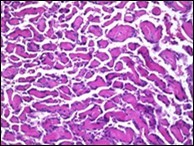

On microscopy, superficial squamous epithelial surface is intact. Sub-epithelial connective tissue stroma exhibits slit-like, vascular spaces. Upon extended magnification, multiple, intravascular papillary projections encompassed within a hyalinised stroma are discerned. Centroidal calcification appears in combination with intravascular, papillary endothelial cell proliferation, lined with singular layer of endothelial cells devoid of cytological atypia6, 7.

Characteristically, the vascular neoplasm denominates numerous papillae within blood vessels. Papillae are coated with singular or dual layer of flattened endothelial cells with an encompassing hyalinised, fibrous tissue core. Vascular lumen is distended with thrombosis. Foci of haemorrhage with fibrinous and purulent exudate are discerned. Tumour perimeter depicts inflammatory granulation tissue. Cholesterol clefts and focal reactive bone formation may concur. Extraneous squamous epithelium may be discontinuous and ulcerated. The neoplasm is devoid of features of malignancy4, 6.

Numerous micro-calcifications can be observed within the lesion which may engender vascular occlusion and tissue necrosis6. Figure 1, Figure 2, Figure 3, Figure 4, Figure 5, Figure 6, Figure 7, Figure 8.

Figure 3.Papillary endothelial hyperplasia exemplifying papillary configuration with endothelial cell layering and a superimposed stratified squamous epithelial lining 12.